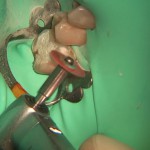

Anestesia locale mediante sistema STA per inserimento di un impianto post-estrattivo a superficie macchinata

Il video propone un intervento di chirurgia implantare durante il quale è stato utilizzato un sistema innovativo per la somministrazione dell’anestetico locale. L’intervento ripreso mostra...